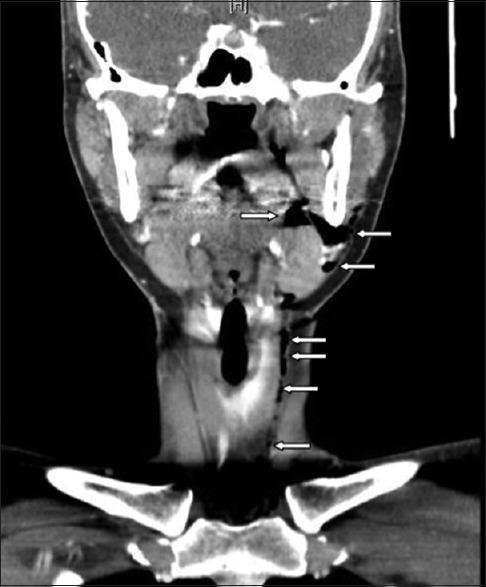

Cervicofacial and mediastinal emphysema due to a dental procedure.

Dental procedures, though commonplace and usually very safe, are not without complications. We report on a case of extensive cervicofacial and mediastinal emphysema after a routine dental procedure, initially masquerading as an allergic reaction in an otherwise young and healthy woman. A review of the relevant literature on this clinical entity is presented, which serves to underscore the need for awareness by the treating clinician of this condition and its potential sequela.

牙科手术虽然常见且通常非常安全,但并非没有并发症。我们报告了一例常规牙科手术后发生广泛颈面部和纵隔气肿的病例,该病例最初在一名年轻健康的女性身上伪装成过敏反应。本文对有关该临床实体的相关文献进行了综述,强调了治疗临床医生认识这种情况及其潜在后果的必要性。